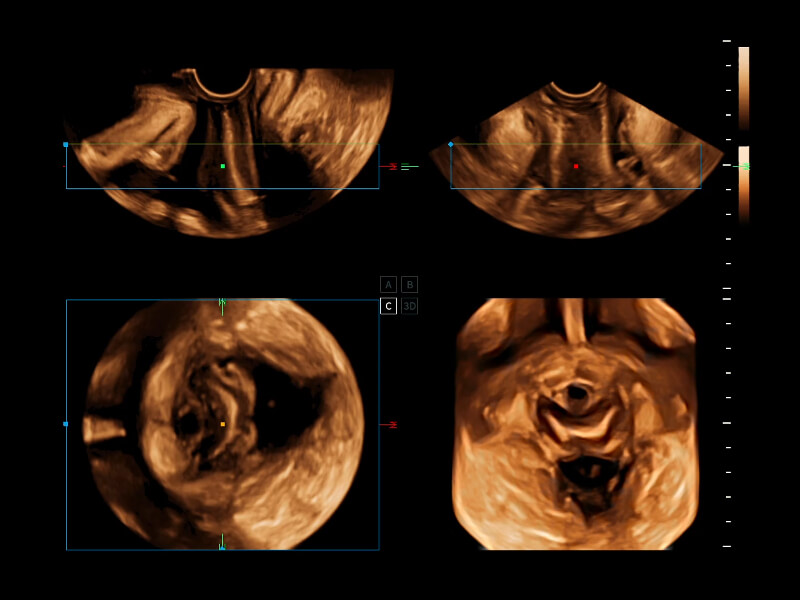

通过光照模型,使二维血流显示出立体的效果,增加血流的敏感性、成束性,减少外溢。可以和其他不同的血流技术联合使用,融合不同技术的优势。轻松应对微小血管,增强血流的立体效果,提升视觉敏感性。